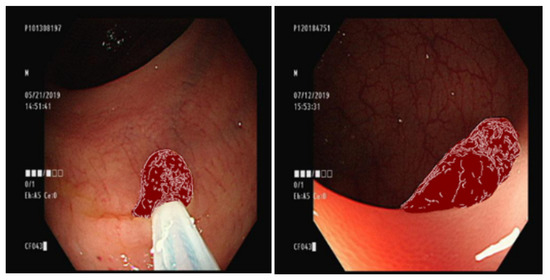

3.2. GAN Training Data Labeling

3.8. YOLO Data Labeling

4.2. Comparison of YOLO Using Different Datasets